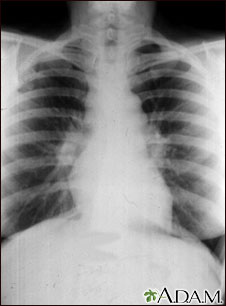

Sarcoidosis, estado I - radiografía de tórax

La sarcoidosis es principalmente una en enfermedad pulmonar. Cuando se encuentra en sus etapas tempranas, la radiografía torácica puede mostrar ganglios linfáticos agrandados en el centro del pecho, cerca del corazón (mediastino).